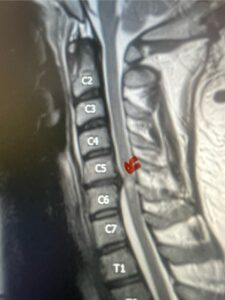

A 37-year-old male police officer complained of a one-month history of difficulty with his balance and leg weakness. He complained of achiness in his legs. He also complained of bilateral arm weakness and numbness of his hands. He was also having difficulty writing due to the weakness. Patient had an MRI of the cervical spine which demonstrated a disc/osteophyte at C56 causing spinal cord compression and concurrent myelomalacia (Fig. 3). Patient underwent an anterior cervical discectomy with a cage and plate (Fig. 4). He tolerated the procedure well with improved numbness and weakness. This is a young person with fairly extensive myelomalacia and a fairly rapid development of symptoms. For this it was felt surgery was indicated. How he will do will depend on how much of his symptoms was caused by the compressive component or intrinsic damage to the spinal cord. As a rule, patients generally improve to some extent quickly; but their recovery of their spinal cord function can sometimes take up to 2 years to realize the extent of their improvement. Patients have to be patient with themselves in terms of their expected recovery.

Fig. 3: Sagittal T2-weighted cervical MRI demonstrating a significant disc osteophyte complex causing spinal cord compression at C 5 6 with extensive myelomalacia (red arrow)